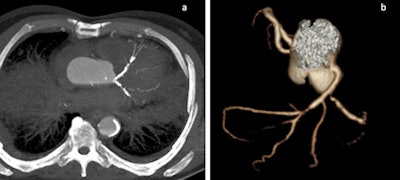

The development of postmortem CT angiography (PMCTA) represents a significant step forward to minimally invasive autopsies, but considerable work still has to be done before it can replace the conventional autopsy, Swiss researchers have found.

The research group in Lausanne is doing multiple studies involving the technique of multiphase PMCTA (MPMCTA). Also, different research projects of the TWGPAM members are ongoing, such as studies about vascular lesions due to road traffic accidents, medicolegal investigations of medical errors using MPMCTA, and the use of MPMCTA for investigating cases of sharp trauma, as well as technical studies to investigate new selective cannulation approaches, etc.